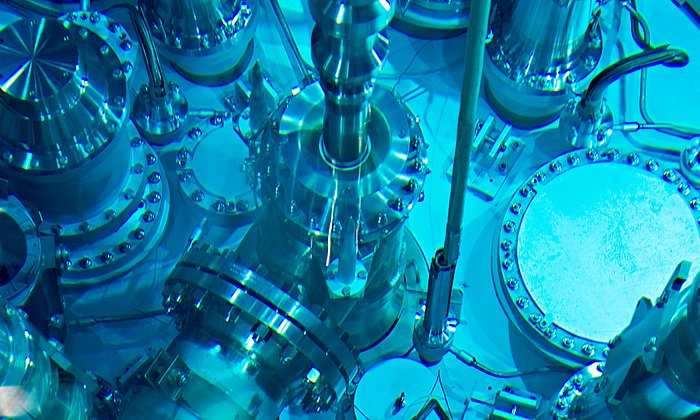

Dem geht nun Josef Lichtinger in seiner Doktorarbeit am Lehrstuhl für Physik der Hadronen und Kerne (E12) der TUM nach. Von der Rechtsmedizin der Ludwig-Maximilians-Universität München (LMU) erhielt er Gewebeproben von Patienten, die mit Lithium behandelt wurden, unbehandelten Patienten und gesunden Vergleichspersonen. Diese setzte der Physiker am Messplatz der Prompten Gamma Aktivierungsanalyse am FRM II einem fokussierten kalten Neutronenstrahl höchster Intensität aus.